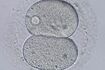

日本産科婦人科学会(日産婦)が集計したデータによれば、'14年に日本で体外受精により誕生した子どもは4万7000人となり、年間出生数が約100万人であることから、21人に1人が体外受精により生まれたことになる。世界一の不妊治療大国に、法律がまるで追いついていないという皮肉。